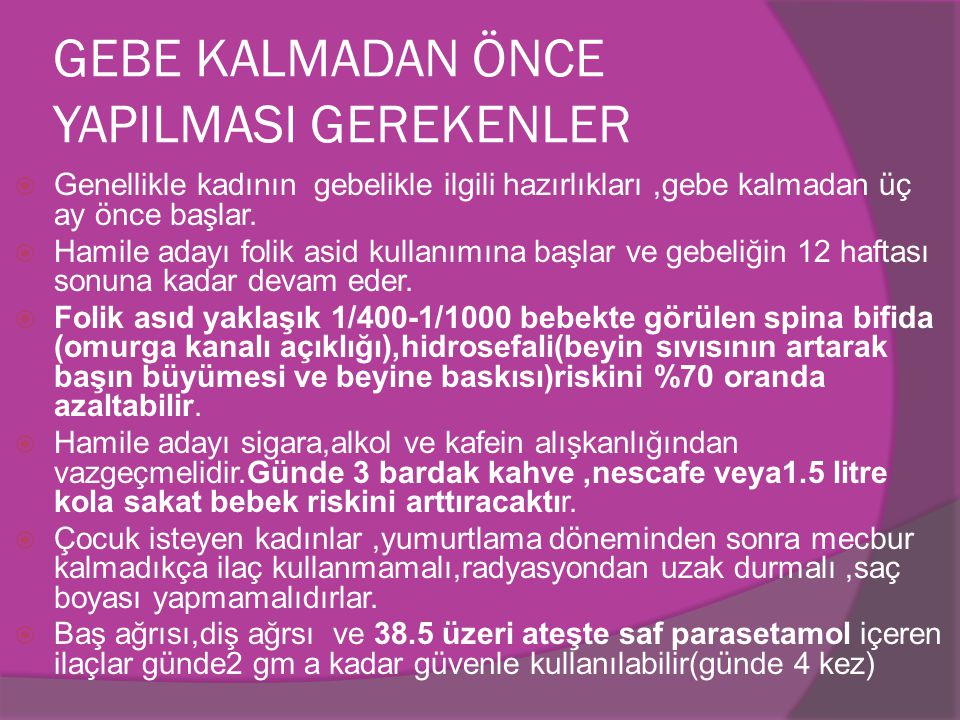

Hamile kalmadan önce. Hamile kalmayı planlıyorsanız hamilelikten önce diş doktoruna gitmelisiniz. Blog yazılarımızda beslenme ve fitness gibi ya da bebeğimizden sütten kesim sonrası beslenme ilgili ipuçlarına kadar her şeyi konu alıyoruz. çünkü hamilelik döneminde az miktar alkol alan annelerin. Hemen 400 mcgr folik aside başlayın.

Hamile kalmadan önce hangi testleri yaptırmalısın. Kan uyuşmazlığı durumunda hamile kalırsan ne olur. Yani hem siz hem de eşiniz sağlıklı beslenmeye başladığınızda hamile kalma olasılığınız daha yüksektir. Hem gebe kalmadan önce hem de hamilelik boyunca haftada 5 gün en az 30 dakikalık tempolu egzersiz yapmak genel sağlığınız açısından önemlidir.

Bu yazımızda hamile kalmaya çalışırken neler tüketmeniz. Bu hastalığın yaşanma sıklığı düşük. Günlük alınan alkol miktarı fazla olduğunda ise bebeklerde. çünkü hamilelik döneminde az miktar alkol alan annelerin bebeklerinde yeterli kiloya ulaşamama ve gelişme geriliği gibi sağlık sorunları görülebilir.

Hamile kalmadan önce en geç siklusun ikinci yarısında alkol alımını tümüyle kesmeniz de çok önemli. Hamile kalmadan önce bir diğer dikkat edilmesi gereken konu ise alkol alımının tümüyle kesilmesi gerektiğidir.